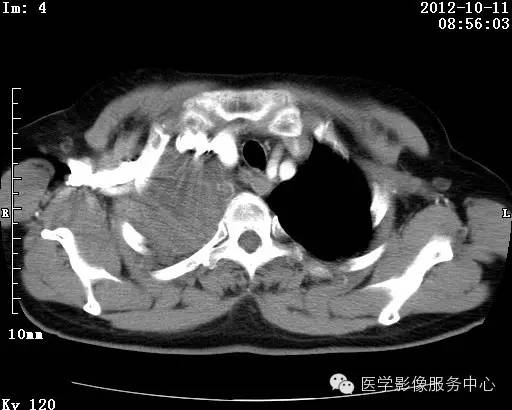

【病例】右肺巨大错构瘤1例CT影像表现

病史:女 65岁咳嗽咳痰 右肺巨大肿块就诊。

错构瘤的发病年龄多数在40岁以上,男性多于女性。 绝大多数错构瘤(约80%以上)生长在肺的周边部,紧贴于肺的脏层胸膜之下,有时突出于肺表面。其特征钙化为爆米花样钙化,内有脂肪软骨成分等等。最常见的部位是胸膜下肺实质内,其次为主支气管或肺叶、肺段支气管内。

理论上肺错构瘤为良性肿瘤,其结节形态、边界、与胸膜关系、与肺门关系、淋巴结肿大及与血管关系均应符合良性肿瘤的特点。

由于不典型错构瘤极易误诊为周围型肺癌和/或结核球,故应与二者鉴别。